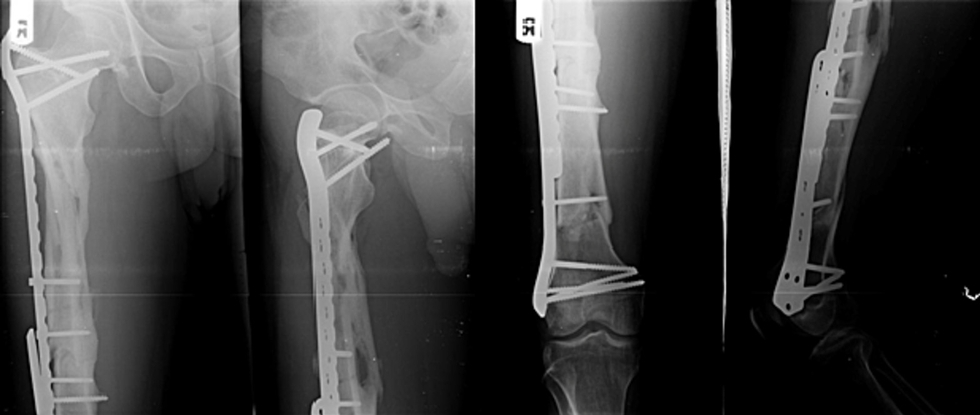

一,背景:复杂股骨骨折是指股骨干合并近端或远端骨折的复合型损伤,仅占所有股骨骨折的5%,治疗极具挑战性。单一内固定方案常难以实现有效固定,现有文献报道了多种治疗方式但疗效参差不齐。本病例报告展示了一例股骨近端严重粉碎性骨折合并远端节段性骨折的患者,其骨折极不稳定需手术治疗。据我们所知,此类复杂骨折类型在文献中极为罕见,关于其固定方式的报道几乎空白。本例采用微创双钢板重叠固定技术,分别于骨折区域上下方应用桥接型股骨近端锁定钢板与刚性股骨远端锁定钢板。二,案例:一名38岁男性患者因交通事故致右大腿闭合性损伤,表现为疼痛、畸形、肿胀及无法负重,至我院急诊就诊。患者为轿车后排乘客,车辆高速行驶时右侧遭受正面碰撞。查体见右大腿明显肿胀伴压痛。右大腿平片显示:右股骨近端节段性粉碎骨折合并远端两处横行骨折(图1)。采用微创钢板接骨术。经三个外侧切口显露股骨(图2)。采用间接复位技术,实现近端骨块的相对对位,并在透视引导下置入两块锁定钢板:股骨近端锁定钢板(PFLP)采用顺行置入,股骨远端锁定钢板(DFLP)采用逆行置入。两钢板重叠区域通过两枚皮质骨螺钉经对应孔道实现骨固定(图3)。术后给予镇痛药物、深静脉血栓预防及抗生素预防治疗,患者恢复顺利。引流管于术后第2天拔除,指导患者使用腋拐行走,右下肢禁止负重。术后第5天出院,嘱2周后返院拆线。在物理治疗师指导下,分别于术后6周及12周开始部分负重及完全负重行走。术后即刻X线片显示内固定位置良好(图4)。桥接钢板固定的近端区域可见四皮质骨痂形成,术后6个月(图5)及9个月(图6)X线片。远端节段性骨折线呈渐进性消失,术后9个月X线片显示骨折线完全消失(图6)。三,总结:此类复杂性股骨骨折属于罕见的高能量创伤。本文报道了采用微创双钢板接骨术成功治疗复杂股骨骨折的案例,结果显示骨折及时愈合且临床疗效良好。文献来源:Kabiru Salisu, Ifeanyi Kene Aghadi,Minimally invasive dual plating of a complex femoral fracture; a case report,Trauma Case Reports,Volume 43,2023,100768,ISSN 2352-6440, https://doi.org/10.1016/j.tcr.2023.100768.